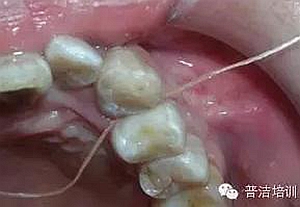

十四、完全就位前去除多余的水門汀,并用牙線和探針仔細(xì)去除牙齒之間的多余材料。

牙線去除鄰面樹脂粘結(jié)劑

鄰面拋光